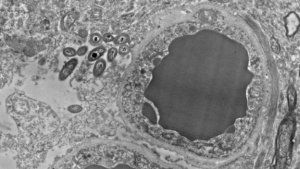

Dr. Rosalinda Roberts and her team from the Psychiatry and Behavioral Neurobiology department at the University of Alabama at Birmingham are responsible for this finding. They studied the brains of 34 people. Half of them were healthy subjects and the other half suffered from schizophrenia. Furthermore, they carried out a parallel study with mice, to rule out that the bacteria appeared only post-mortem or if there could be any error due to contamination.

In both studies, scientists observed the presences of bacteria in human and mice brains in non-infectious or traumatic situations. In fact, they found them in several areas of the brain. Mainly in the substantia nigra, the hippocampus, and the prefrontal cortex, and very little in the striate. In addition, none of the brains they examined showed inflammation.

Main image courtesy of Rosalinda Roberts, Courtney Walker, and Charlene Farmer.